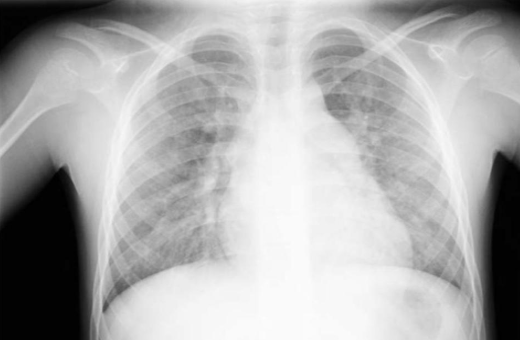

what is this?

alveolar pulm edema